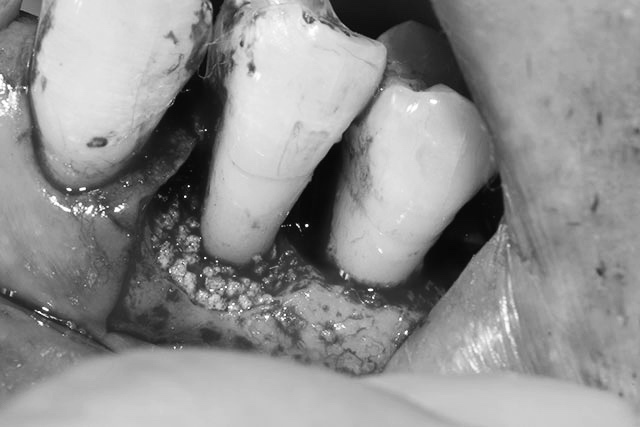

- 骨がなくなった部分に入り込んだ悪い組織や歯石をすべて取り除きます

-

- 人工の骨とエムドゲインの併用行い膜を置いて閉じます

この間も仮歯があるため見た目を気にせず過ごしていただけます。